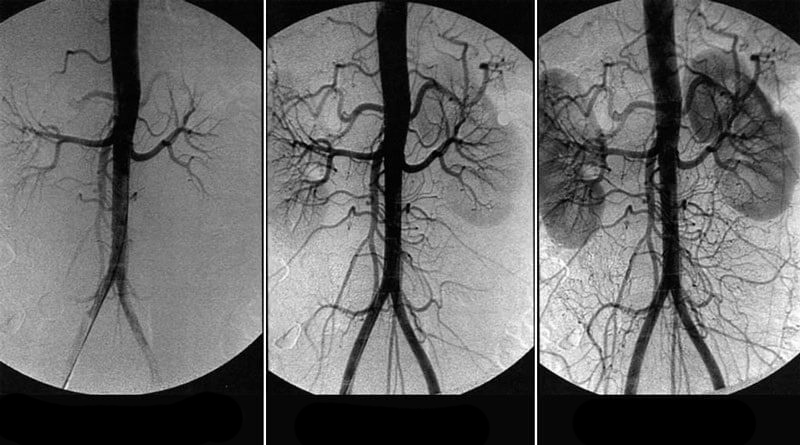

• Paciente: Mujer, 67 años. Al inicio de había lesiones extensas en la aorta torácica y abdominal con depósitos de colesterol. Trastornos circulatorios de los órganos abdominales, pulmones y bronquios.

• Complicaciones concomitantes: Hipertensión de grado III, hinchazón de las extremidades inferiores, varices, arritmia.

• Quejas del paciente: Dolores de cabeza, mareos, acúfenos, dolores y calambres en las piernas, problemas de sueño, presión arterial hasta llegar a las crisis hipertensivas.

• Indicación: Carditone, 3 veces al día después de las comidas. Visita de control a los 30 días y a los 60 días.

Inicio de administración de Carditon

30 días de administración

60 días de administración

Resultados del prevención

Los resultados del prevención de 30 días con Carditone son los siguientes:

• La presión arterial se normalizó en 130-13985-89. Que es el límite superior de lo normal;

• no se observa ninguna hinchazón;

• no se observan manifestaciones de varices;

• no hay arritmia, pulso estable a 73 lpm;

• los dolores de cabeza y los acúfenos no te molestan después de la primera semana de tomar el suplemento;

• el sueño se normaliza;

• la agudeza visual mejoró;

• el tono y el bienestar general mejoraron considerablemente.

• Paciente: Hombre, 51 años. Al inicio de presentaba una importante alteración circulatoria cerebral.

• Complicaciones concomitantes: Hipertensión arterial, córnea borrosa, osteocondrosis cervical y torácica, prostatitis crónica, hemorroides agudas.

• Quejas del paciente: Dolores de cabeza, alteración de la visión, deslumbramiento en los ojos. Debilidad y apatía general, falta de voluntad para hacer algo. Bajo rendimiento, incapacidad para concentrarse durante mucho tiempo, problemas con la potencia.

• Indicación: Carditone, 3 veces al día. Visita de control a los 30 días y a los 50 días.

Inicio de administración de Carditone

47 día de administración de Carditone

Los resultados del prevención de 1,5 meses con Carditone fueron los siguientes:

• la presión arterial se estabilizó por completo;

• los dolores de cabeza desaparecieron;

• aumento de la capacidad de trabajo y actividad;

• la potencia mejoró considerablemente;

• las hemorroides desaparecieron;

• los dolores de espalda, cuello y articulaciones desaparecieron;

• los síntomas de la prostatitis no aparecen.